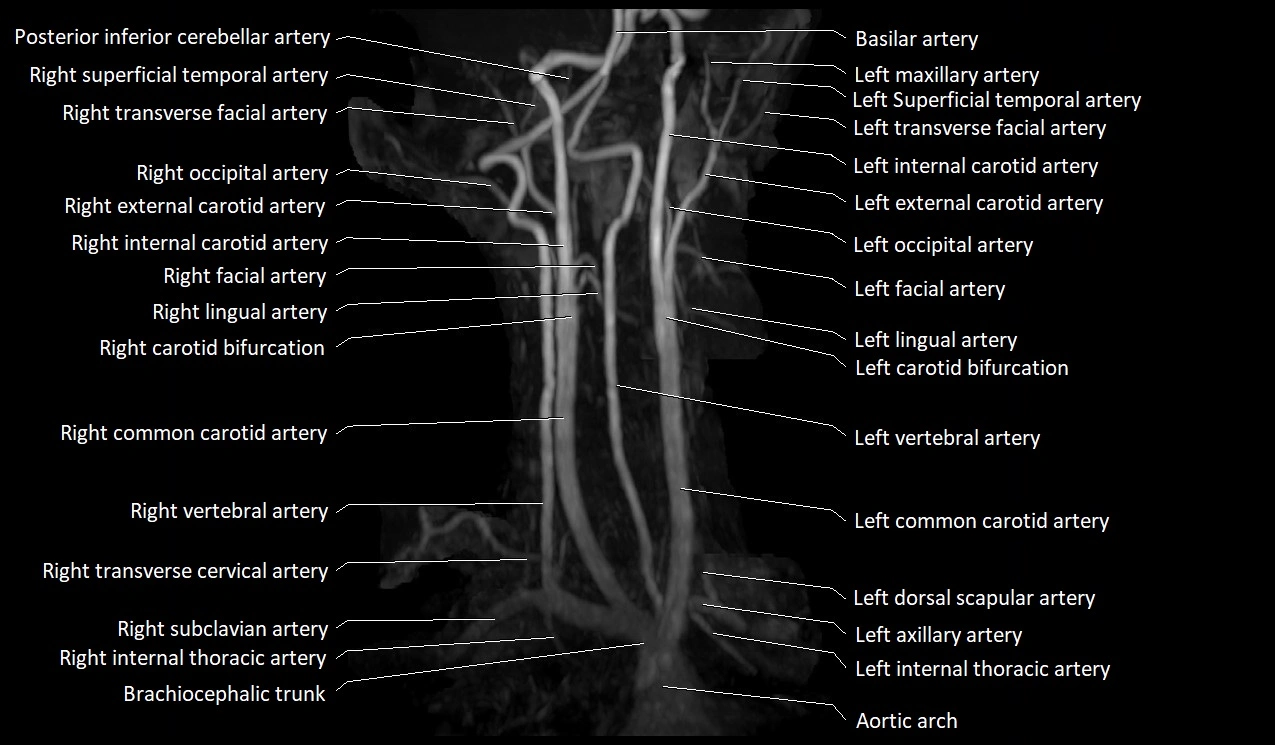

MRI images

image